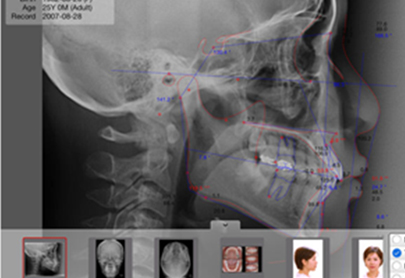

3D구강스캐너와 CBCT등을 통해 수집한 데이터를 토대로

치아 뿌리의 특성, 얼굴의 골격, 비대칭 정도, 치아의 이동 예측량, 치아의 교합을 꼼꼼하게 분석하고

교정의 치료 결과예측을 위해 삼차원적으로 시뮬레이션하여 오차 없는 치료 계획을 수립합니다.